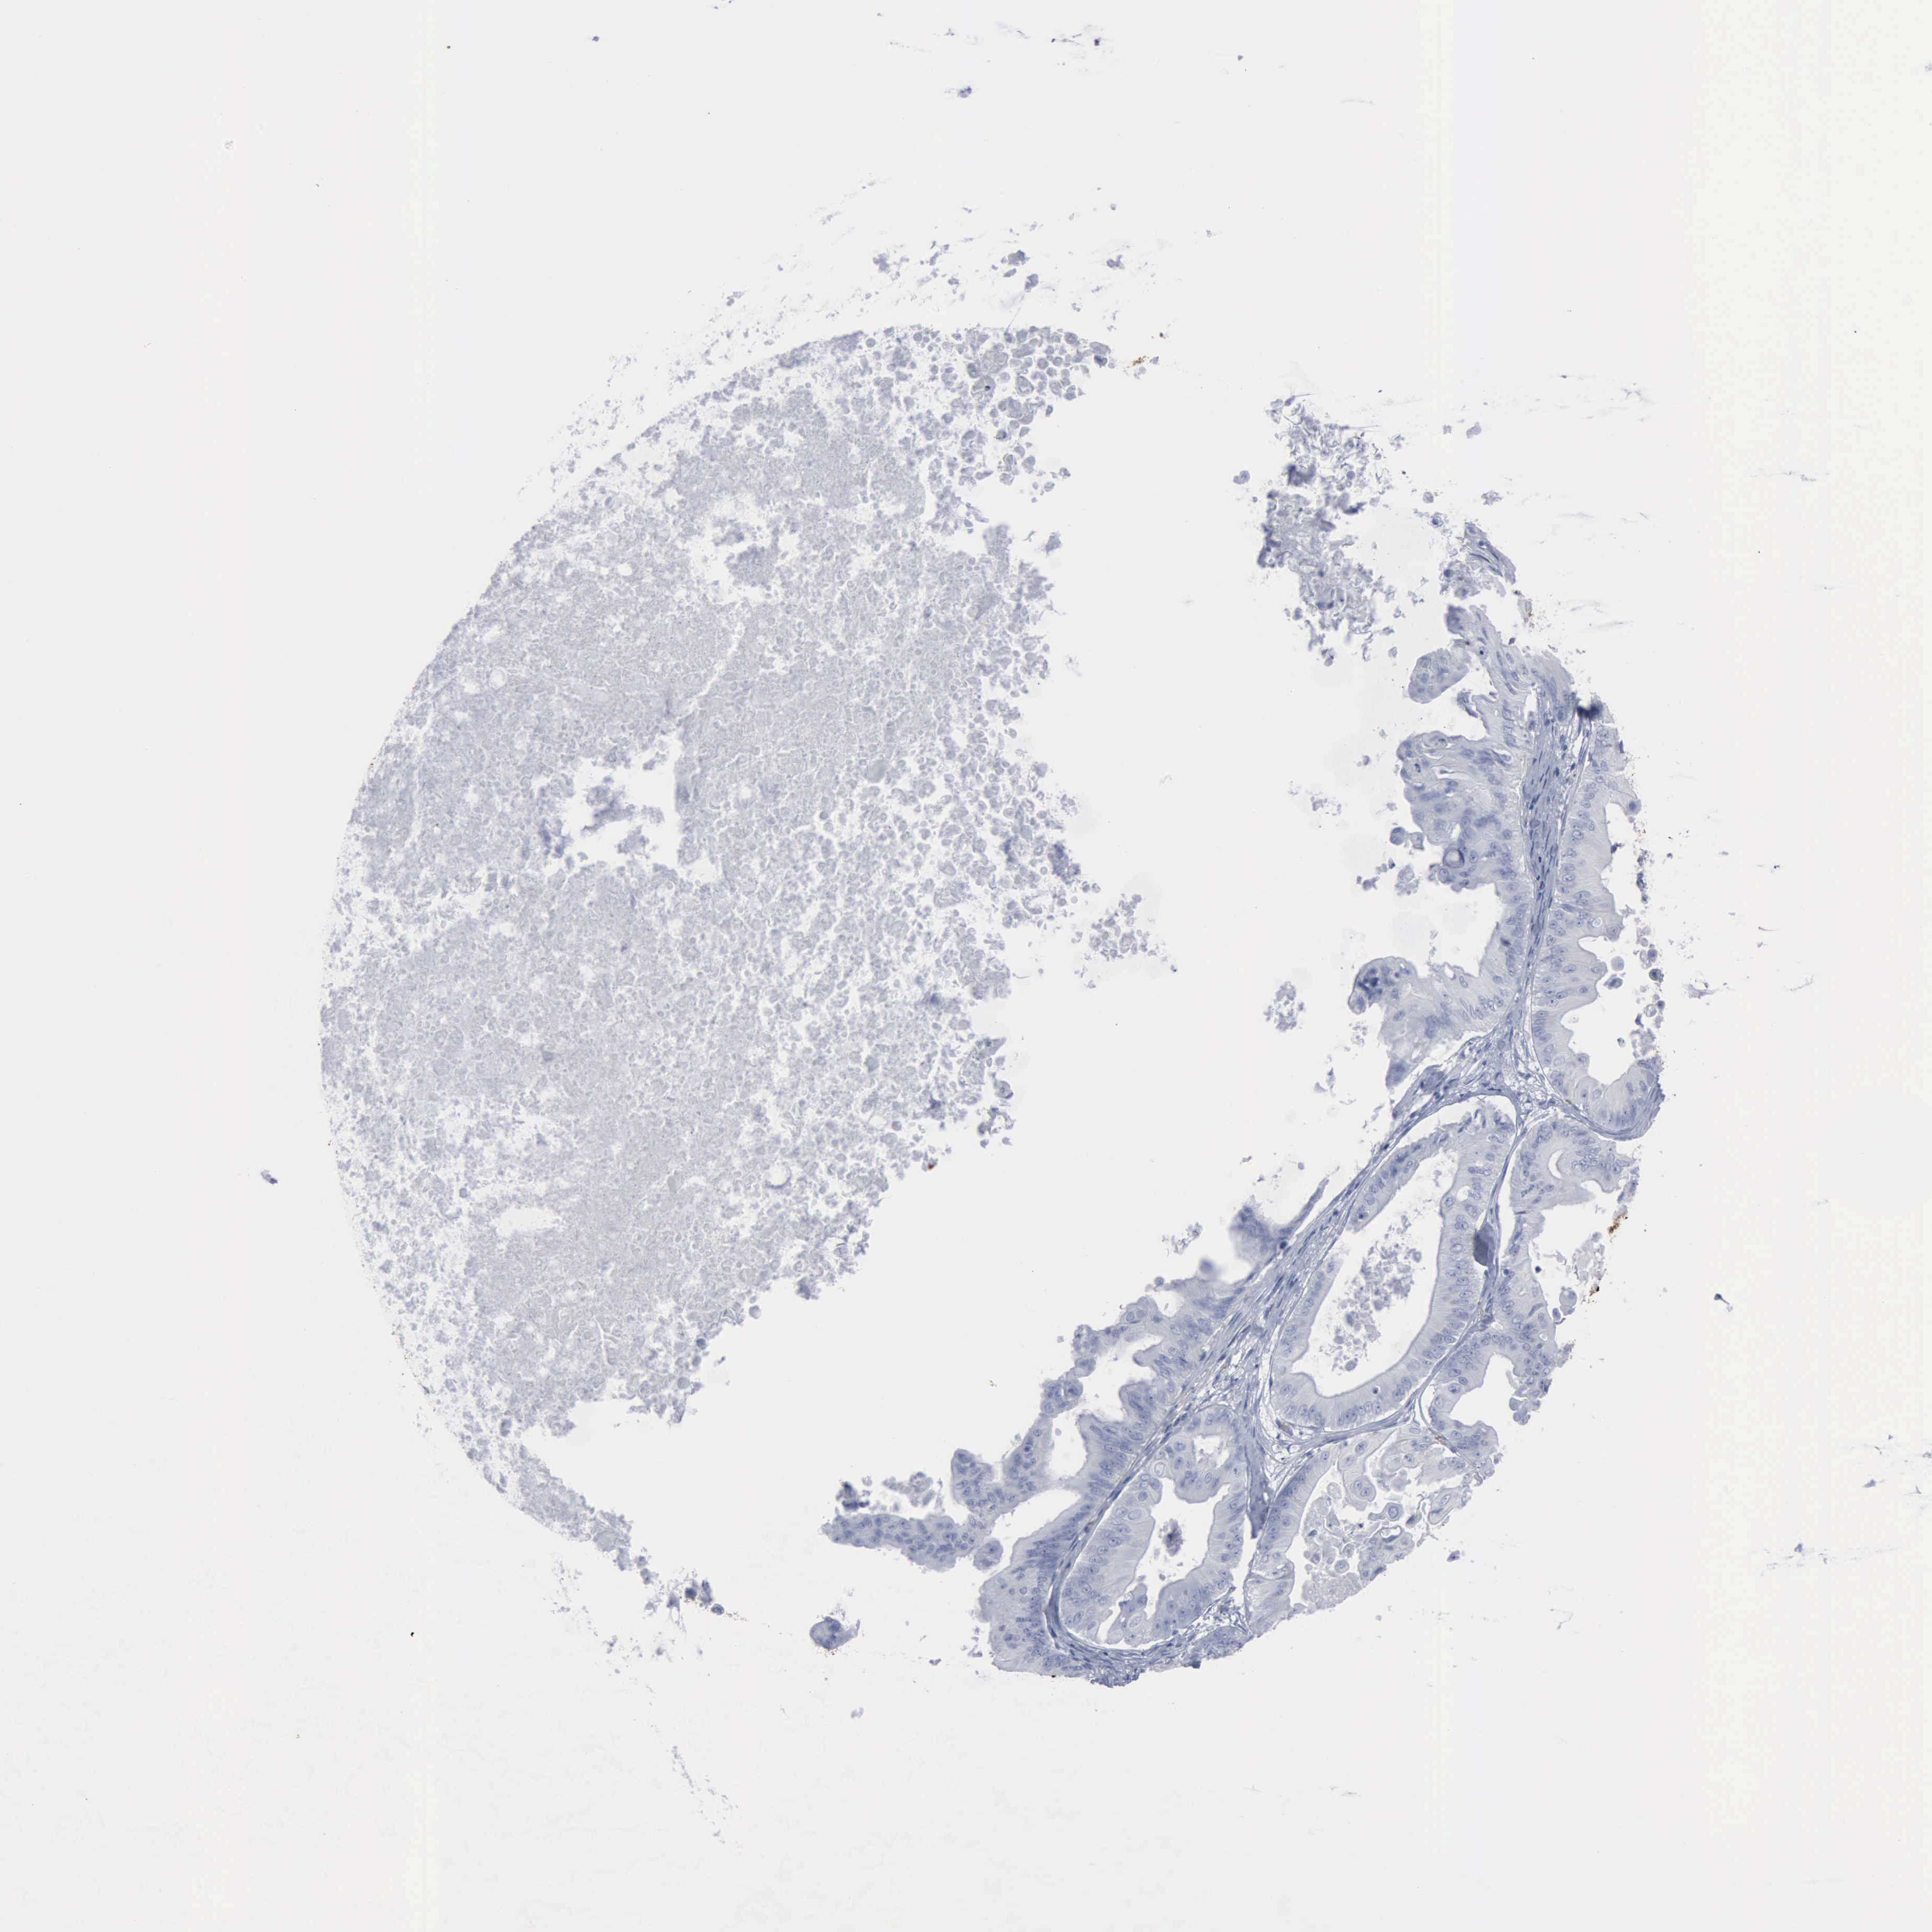

OVARIAN CANCER - Protein expressioni

A mouse-over function shows sample information and annotation data. Click on an image to view it in a full screen mode. Samples can be filtered based on level of antibody staining by selecting one or several of the following categories: high, medium, low and not detected. The assay and annotation is described here.

Note that samples used for immunohistochemistry by the Human Protein Atlas do not correspond to samples in the TCGA dataset.

Antibody stainingi

Antibody staining in the annotated cell types in the current human tissue is reported as not detected, low, medium, or high, based on conventional immunohistochemistry profiling in selected tissues. This score is based on the combination of the staining intensity and fraction of stained cells.

Each image is clickable and will lead to virtual microscopy that enables deeper exploration of all samples and also displays staining intensity scores, fraction scores and subcellular localization as well as patient and tissue information for each sample.

Antibody CAB000361

Cystadenocarcinoma, mucinous, NOS

Carcinoma, endometroid

Cystadenocarcinoma, serous, NOS